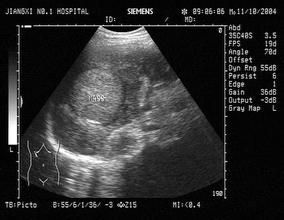

5.超聲顯像可顯示2cm的腫物。有症狀者,各項定位診斷方法的陽性率可達70%~90%。

①多有肝病背景,B肝或C肝標記物常陽性;②常伴肝硬化;③血AFP常明顯升高;④B超常顯示實質不均質光團,部分伴有暈圈;⑤彩超常顯示豐富的血流,可測及動脈頻譜,阻力指數常大於0.60;⑥CT增強掃描的動脈相常顯示增強效應,但靜脈相增強效應減弱,呈現“快進快出”的特點;⑦門靜脈癌栓幾乎是原發性肝癌的特徵性徵象。